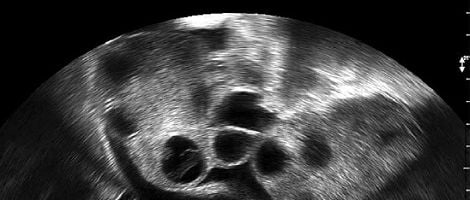

-O número de folículos necessários para determinar a existência de uma baixa resposta vária de autor para autor. Alguns defendem que esse número deve ser menor de 3 e outros que deve ser menor de 6.

-Quanto ao número de ovócitos, existem também várias opiniões. Contudo, o seu número é de entre 3 e 6 ovócitos recuperados.

-Considera-se que existe uma baixa resposta ovárica quando se recupera um baixo número de ovócitos com doses de FSH inferior a 3000UI.